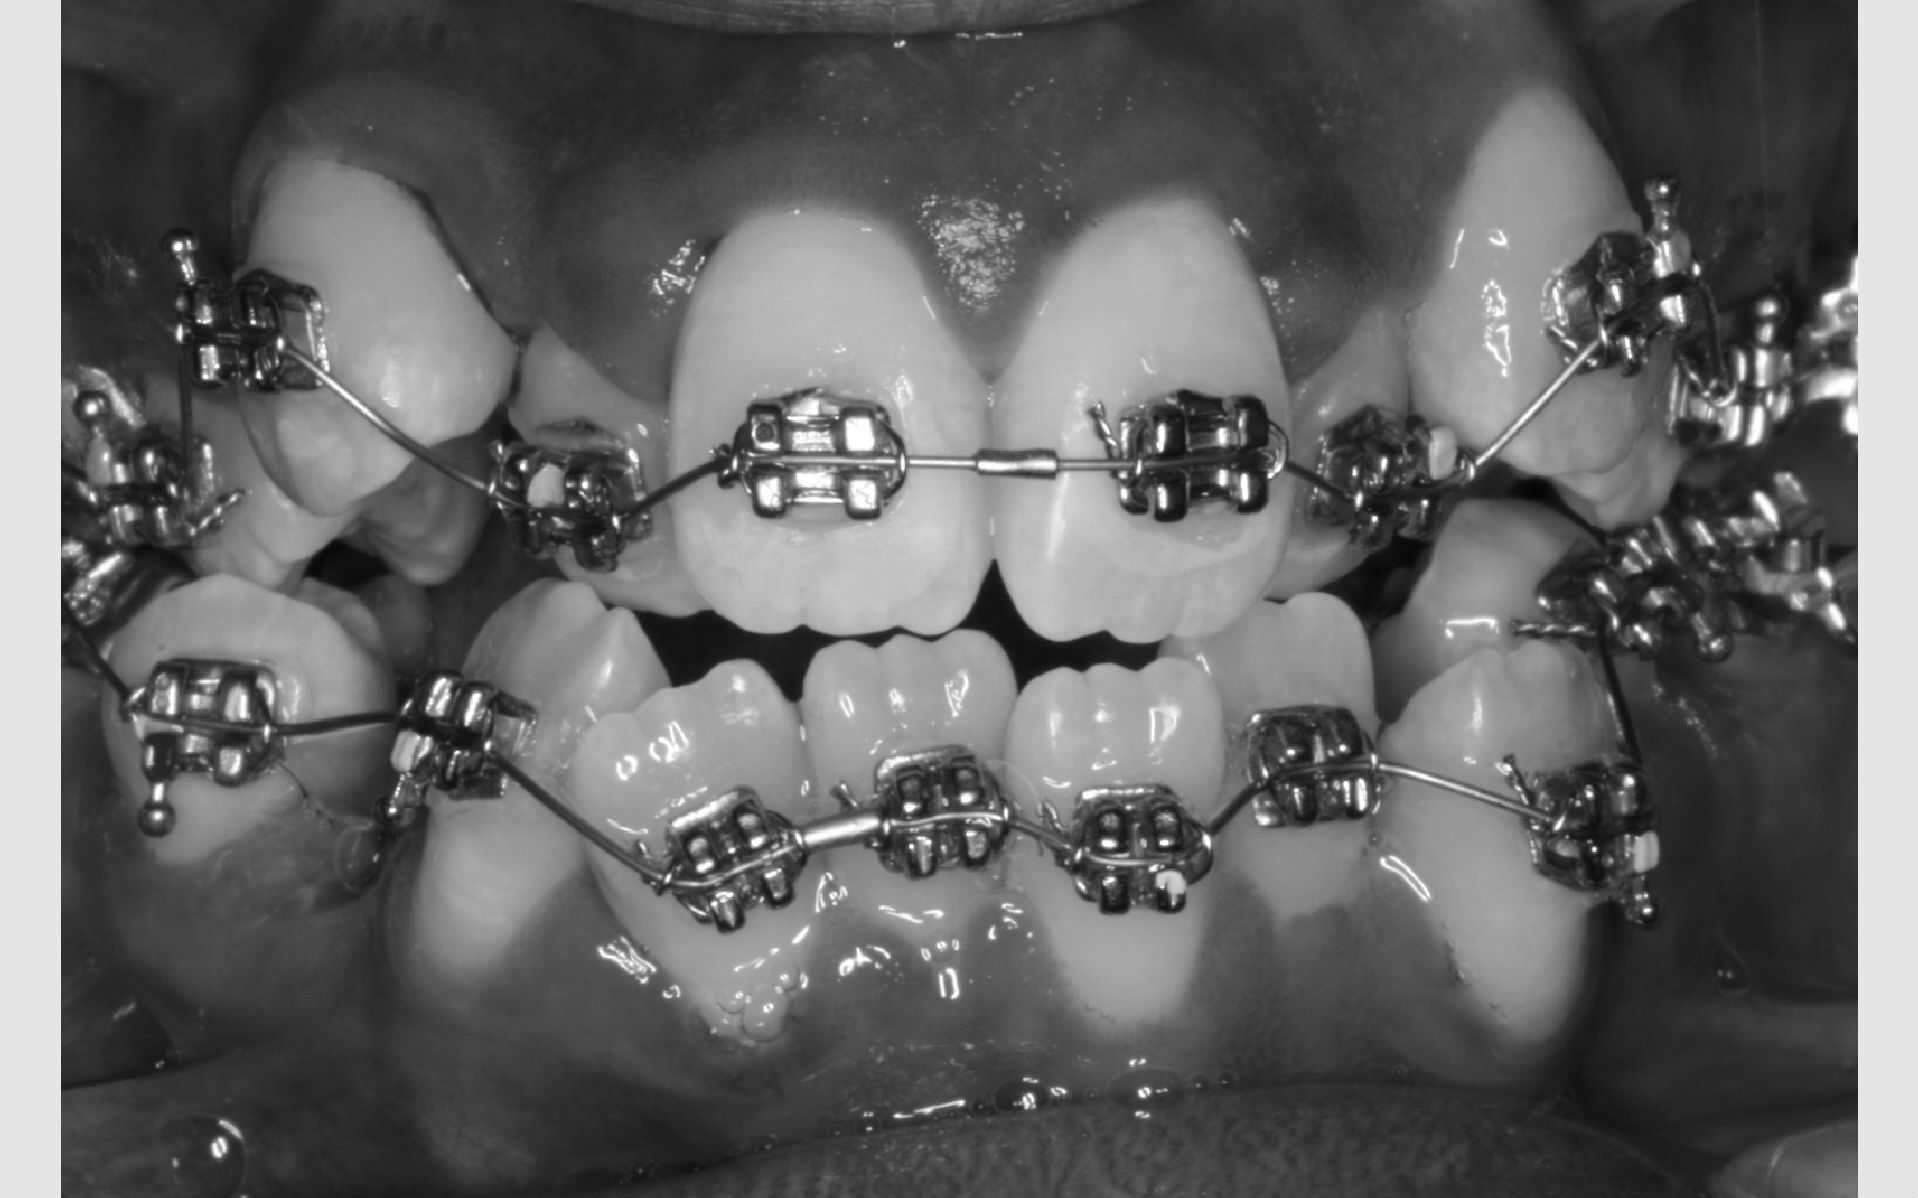

Kontrol af din bøjle foregår på Tandreguleringsklinikken cirka hver 6. uge. Det varierer lidt gennem behandlingen afhængig af, hvilken fase, du er i. Ofte bliver du bedt om at bruge nogle elastikker mellem bestemte tænder. Det er yderst vigtigt, at du følger det, der aftales fra gang til gang, så behandlingen går hurtigst og bedst.

Hvis noget går i stykker

Når du har bøjle på, er det vigtigt, at du spiser med omtanke. Risikoen for huller i tænderne er langt større, når du har bøjle på. Du bør derfor spise sundt og undgå for meget sukker. Hold dig desuden fra hårde og seje ting, der kan beskadige bøjlen.

Får du bidt en lås af eller deformeret buen, er det vigtigt, at du ringer til Tandreguleringsklinikken og får en ekstra tid, så bøjlen kan blive repareret. Bøjlen skal hele tiden være i orden for at fungere optimalt.